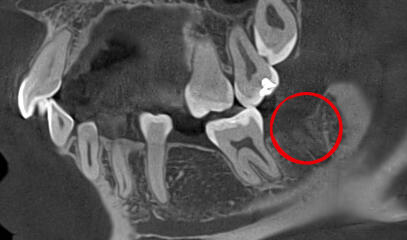

Перед удалением стоматолог назначает рентген (X-ray) или компьютерную томографию (КТ) для оценки положения зуба и анатомических особенностей, особенно в случае непрорезавшихся или неправильного положения зубов.

Непрорезавшиеся зубы мудрости часто имеют аномалии, которые усложняют удаление, такие как разветвленные, изогнутые корни или разрушенные коронки, что затрудняет захват щипцами. Для правильного удаления необходимы рентгеновский снимок и полный медицинский анамнез пациента.